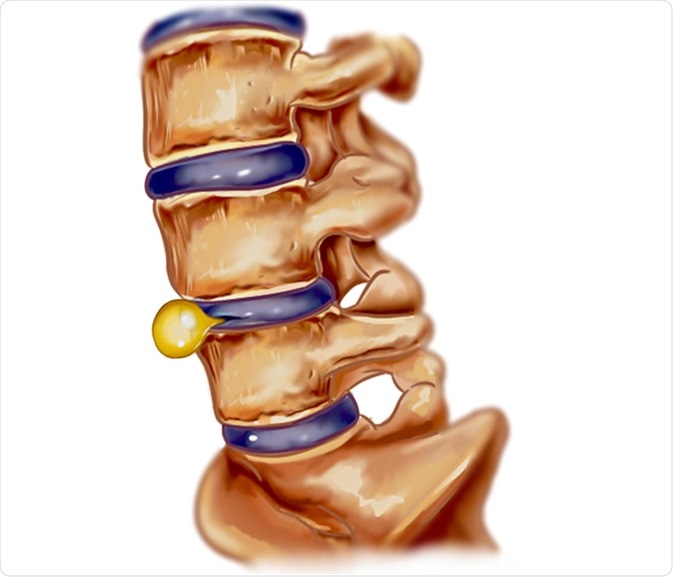

Slipped disc

Pelvic intervertebral disc prolapse or slipped disc is a condition in which the soft cushion of tissue present between adjacent spinal bones pushes out. A slipped disc can irritate nearby nerves, resulting in pain and numbness or weakness in an arm or leg. The pain worsens after sitting or standing, walking short distances, and with certain movements. The pain is more severe at night, and is accompanied by burning, tingling, and aching sensations on the affected area.

Slipped disc illustration. Image Credit: corbac40 / Shutterstock